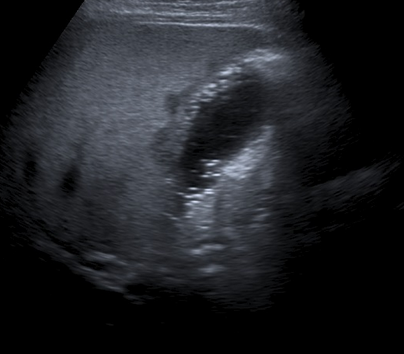

• US

• Linear hyperechoic structures

• Dirty shadowing